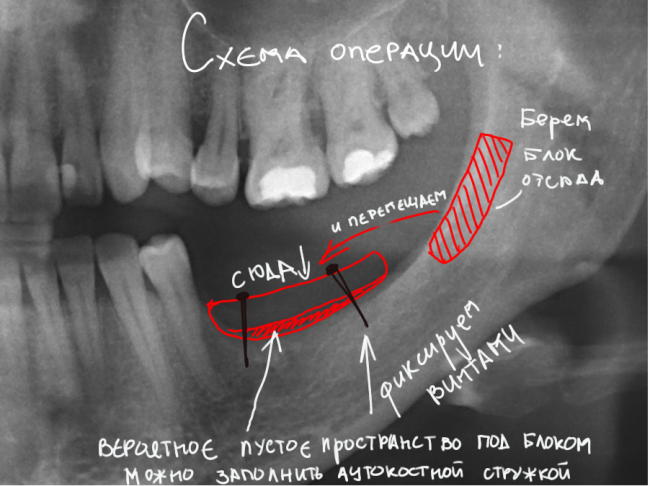

В общих чертах, схема будущей операции выглядит так:

Остановлюсь лишь на некоторых моментах:

- Способ проведения операции — аутотрансплантация костного блока из ретромолярной области и ветви нижней челюсти с последующей фиксацией винтами. Это наиболее предсказуемый метод вертикальной остеопластики, дающий максимум положительных результатов. Ни один метод с использованием ксенотрансплантатов (Bioss, Cerabone, Easygraft и т. д.) такой статистики не дает.

- Под блоком, вероятно, будет небольшое пустое пространство вследствие неплотного соответствия поверхностей. Его заполняем аутокостной стружкой, взятой из того же участка, что и блок. В этом случае использование барьерной мембраны (BioGide, Jacon и т. д.) ОБЯЗАТЕЛЬНО.

- Пересаженный костный блок также подвержен атрофии — за 3 месяца мы потеряем, порядка 20-30% от первоначального объема. Поэтому блок берется с запасом, учитывающим возможную атрофию. НО есть один нюанс — это верхние выдвинувшиеся зубы. При излишней высоте блока пациентка будет «кусать» область операции верхними зубами, а это чревато осложнениями. Ну и про дефицит слизистой оболочки нельзя забывать. Выбираем компромиссную середину.

- Забор костного блока целесообразнее сделать через ту же рану, что и основную операцию. Хотя с подбородка или бугра верхней челюсти донорский блок брать удобнее, мы думаем. в первую очередь, о комфорте пациентки — за одной раной, пусть и большой, ухаживать легче, чем за двумя.

- Качество швов и слизистой оболочки. Расхождение швов серьезно увеличивает риски потери блока, процентов на 20-25. А при использовании ксеногенных материалов — на 100%.